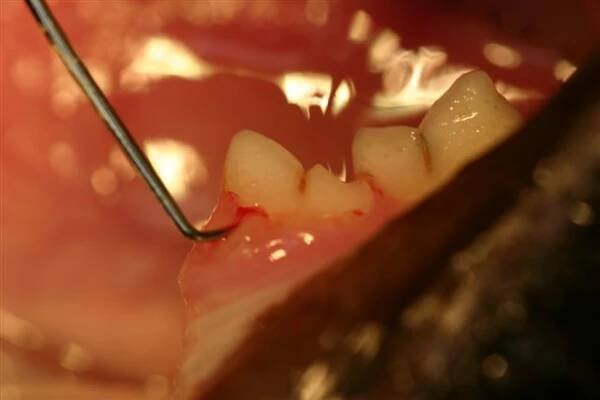

Existuje několik zákroků, které byste v zubařském křesle jen těžko čekali. Transplantace je bezpochyby jeden z nich. V jakých situacích se k takovému zásahu stomatolog uchýlí? Jak celá operace probíhá a jaká jsou rizika?

Čelistní chirurgie: Extrakce semiretinované 8+ Beinovou pákou